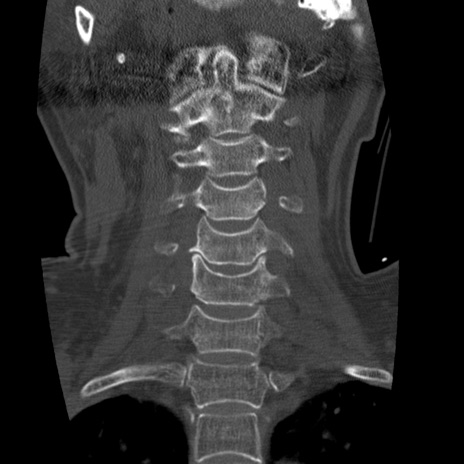

症例50 頚椎CT(冠状断像)

頚椎CT